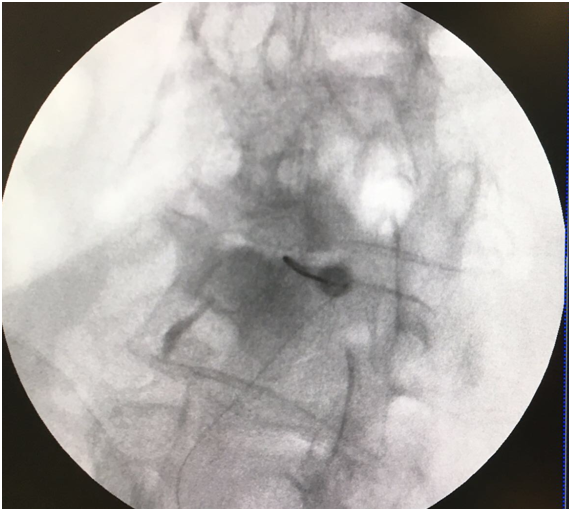

A transforaminal (TF) block was proposed at L2, L3, and L4 on the left side. After explaining the technique and its possible complications, which include the risks of infection, bleeding, and allergic reactions, oral and written consent was obtained, and the nature of the technique was explained to the patient, i.e. to perform a diagnostic block to determine the source of her pain. The technique was performed in the operating room on an outpatient basis, with standard monitoring according to SEDAR [Spanish Society of Anesthesia, Recovery, and Pain Therapy] standards (including EKG, O2 saturation, and non-invasive blood pressure tests) and radiological monitoring. The interventionist located the treatment sites with the patient lying in the prone position, using an abdominal pillow to reduce lumbar lordosis. During the procedure, a Yale 22G spinal needle was used for all treatment sites. The area was cleaned with chlorhexidine solution and misted so that the surgical field was completely sterile, with the area to be treated left exposed. A TF block was performed at the level of L2 without difficulty, although the TF block at the level of L3 was very difficult due to the patient’s anatomy, which presented with a lateral displacement of L3 and abundant osteophytes on the vertebral body, making it very difficult to visualize the entry point through the foramen. For this reason, it was deemed more appropriate to enter through the L3-L4 facet joint. In order to perform the block at this location, the C-arm of the fluoroscope was tilted obliquely until the spinous process was brought to the contralateral pedicle axis, or until the superior articular process could be seen in the middle part of the intervertebral disc, forming the famous “Scottie dog” sign, at an oblique inclination of approximately 20-30º; the double contour of the intervertebral disc was corrected with a craniocaudal inclination of the C-arm. After this maneuver, the X-ray was inclined craniocaudally (20º) to separate the iliac crest and allow entry into the foramen, according to the usual technique.13 Given the impossibility of visualizing the entry point, the C-arm was forced to incline in both directions (obliquely and craniocaudally), without achieving visualization (Figure 1). As seen in Figure 2 the only entry point that allowed access to the desired target was through the zygapophyseal joint. To perform this approach, this joint was centered and the C-arm was rotated until the facet joint could be visualized correctly. The target for this type of approach is the middle part of the joint. The approach was done in “tunnel vision” (the needle was positioned with its axis parallel to the X-rays being emitted), advancing along this direction until it reached the location of the L3 DRG. The depth of the needle was checked using a lateral X-ray view (Figure 3). The needle was pushed slightly deeper through the facet joint until it reached the epidural space and the dorsal root ganglion of L3. Entry into the joint is perceived as a loss of resistance as the needle penetrates the synovial membrane. Once it entered into the joint, the location was verified by injecting 0.1 to 0.3 mL of contrast medium (Figure 4). After verifying that the needle was placed perfectly, local anesthetics and corticosteroids could be injected. In this case, the interventionist used 0.25% bupivacaine and triamcinolone, in an amount not exceeding 1-2 mL.

Figure 4 Contrast is used to visualize the location where the root exits (1) with the needle in the interapophyseal joint (2).